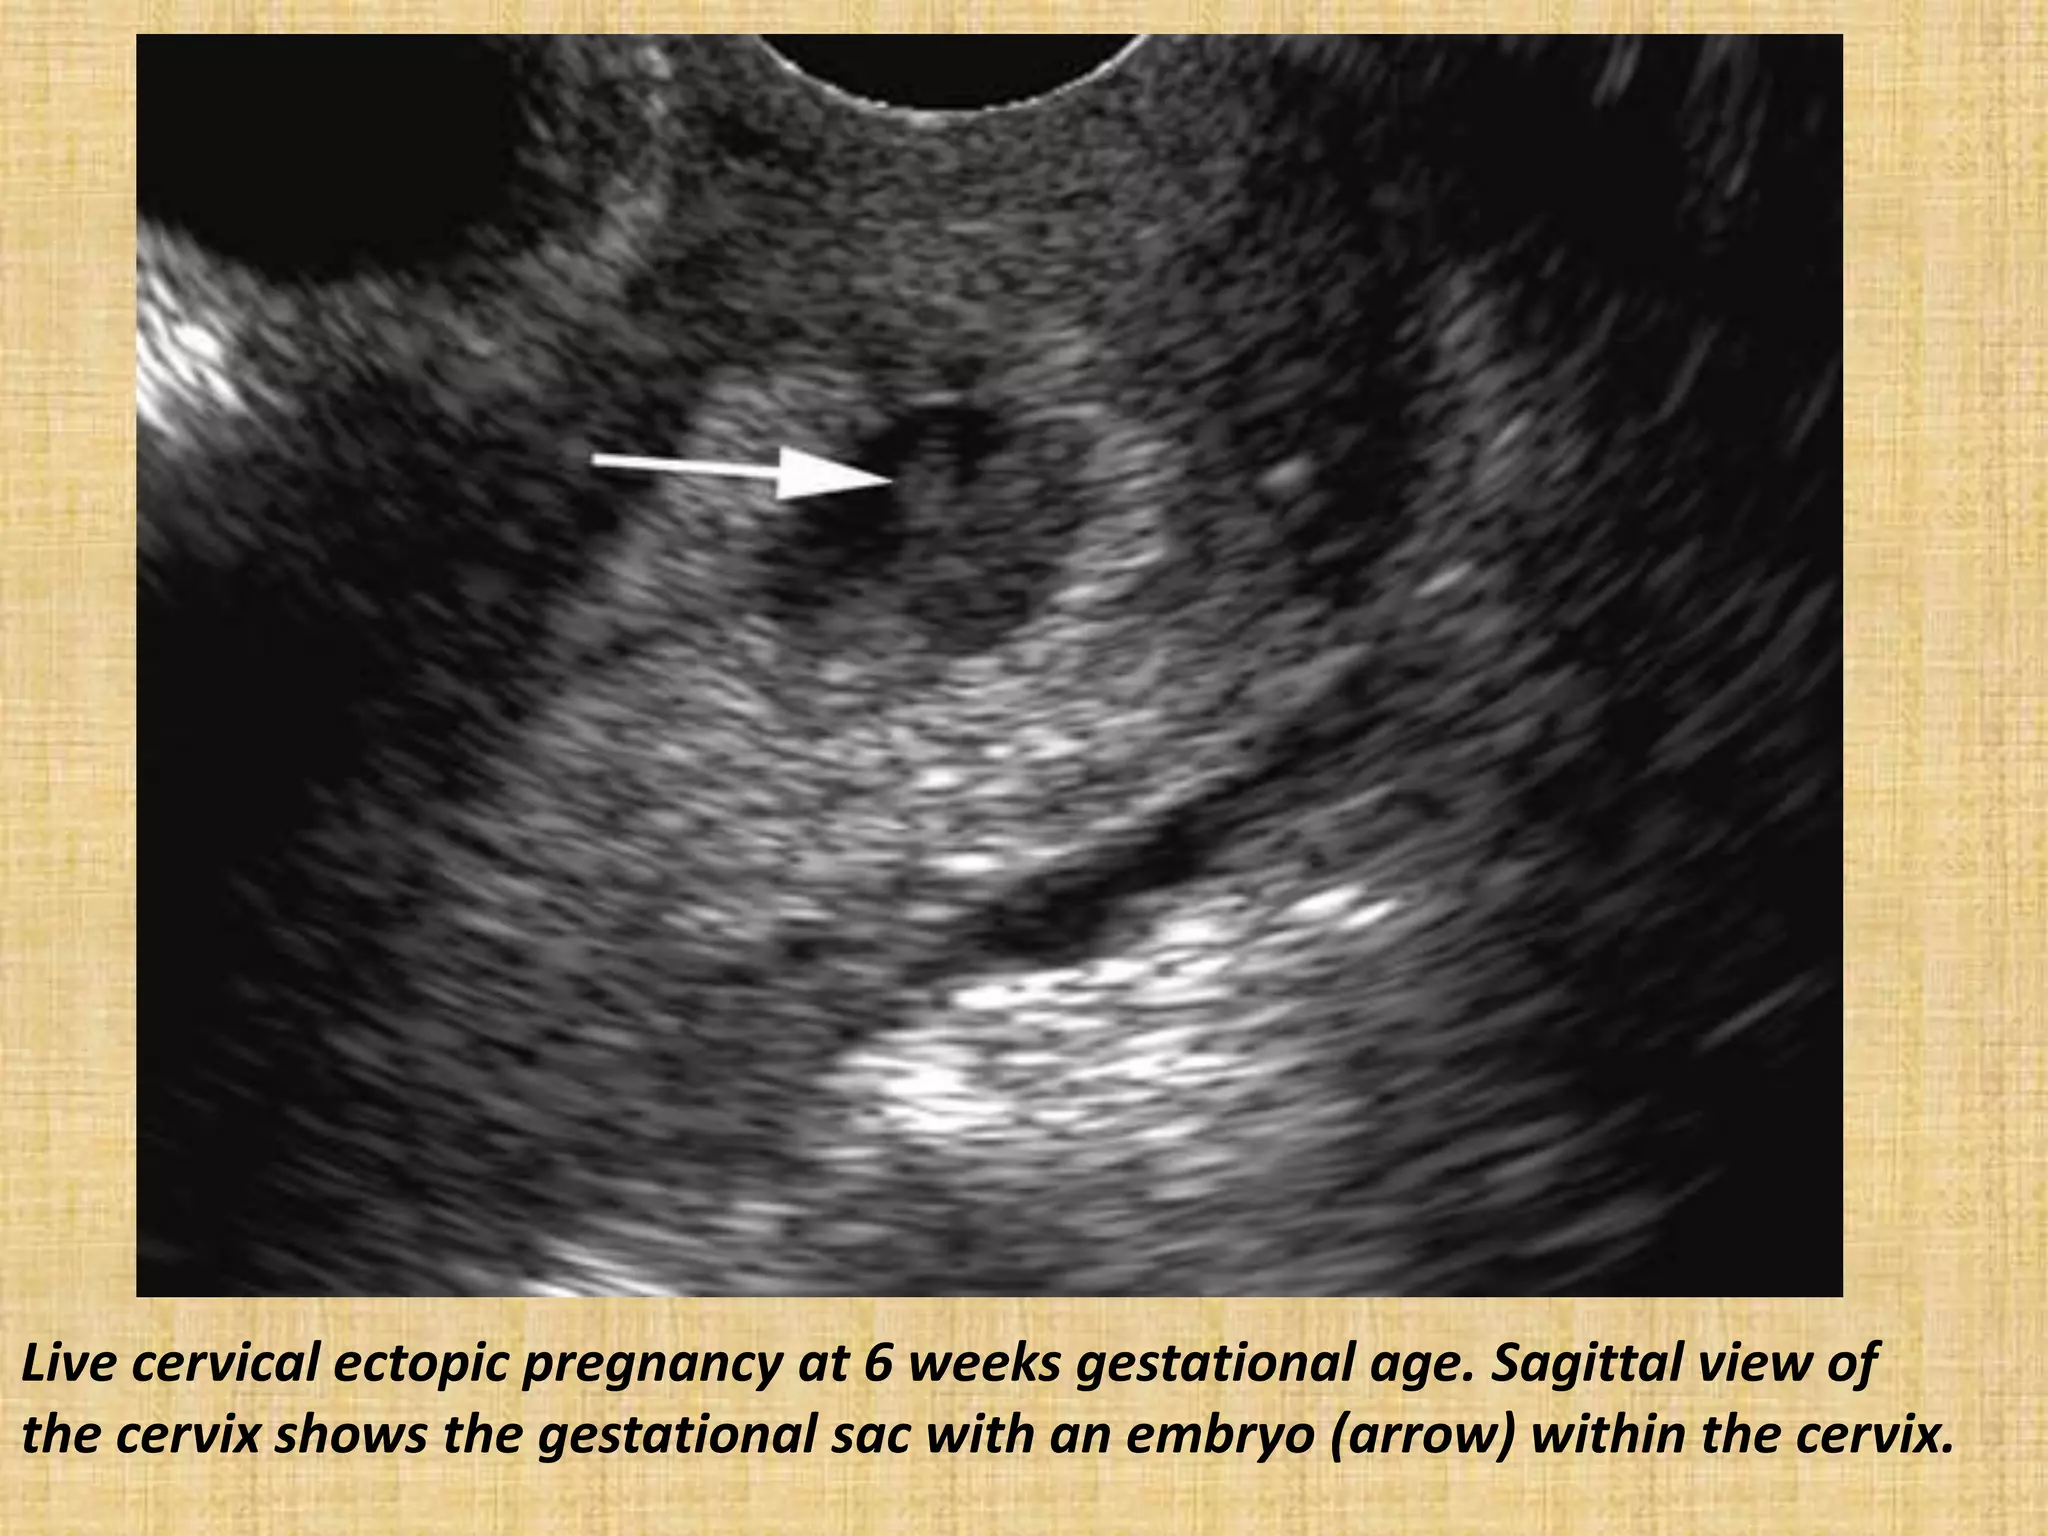

Live cervical ectopic pregnancy at 6 weeks gestational age. Sagittal view of

the cervix shows the gestational sac with an embryo (arrow) within the cervix.